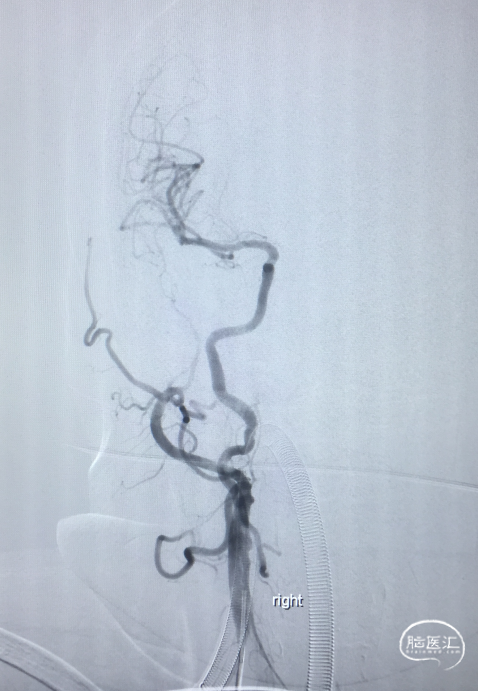

术前DSA:LICA正侧位及工作角度造影显示前交通动脉瘤

术前DSA:RCCA正侧位造影